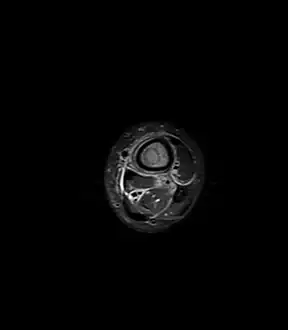

Axial T1-weighted MRI pre-contrast enhancement showing that the intramedullary collection is T1-hyperintense suggesting proteinaceous viscous fluid consistent with infection. -

Axial T1-weighted fat-saturated MRI image following IV gadolinium contrast demonstrating the intramedullary lytic area seen on radiography to be ring enhancing consistent with a purulent fluid collection. Extensive circumferential periosteal enhancement is noted. There is also substantial bone marrow enhancement. -